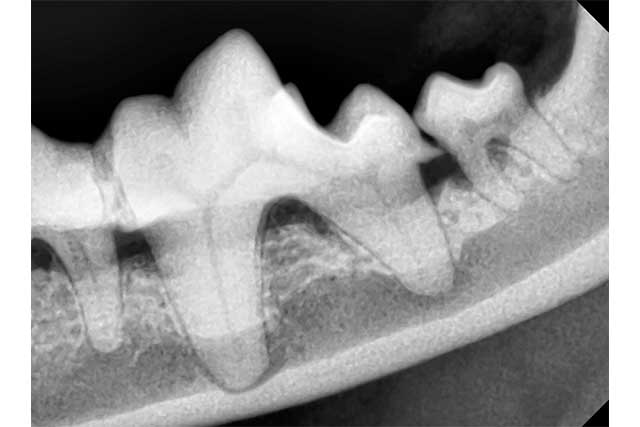

肉眼では見えない歯の根元の状態を、歯科専用のレントゲン装置で詳細に確認します。これにより、「抜くべき歯」と「残せる歯」を的確に判断し、無駄のない迅速な手術を可能にします。